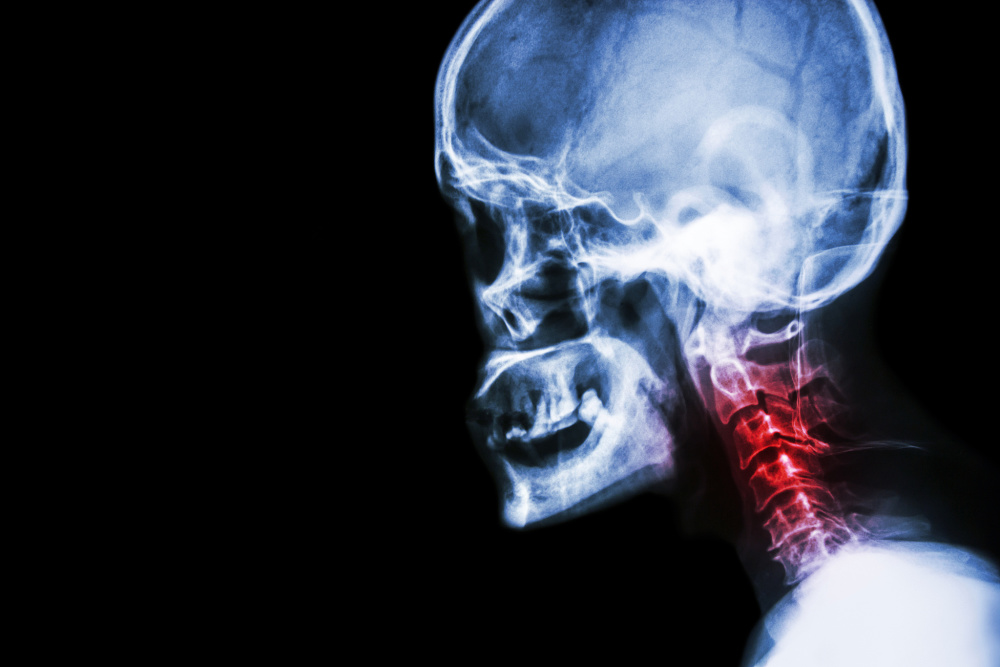

3、颈椎问题:平时就容易出现颈椎失稳、颈部酸痛、活动受限,上肢麻胀等不适症状,如果睡眠时不加以注意,亦可引发落枕。实际上,落枕也是颈椎病的一种,两者可互为病因。

所谓的不稳定状态,就是指颈椎周围肌肉张力、关节囊或韧带的失衡导致脊椎椎骨间小关节易发生相互移动的现象。颈椎周围附着了很多肌肉和韧带,这些软组织的相互平衡共同保证了颈椎的稳定性。

刚前面提到的各种因素,如睡觉时头部姿势不当、或枕头高低软硬不适合、局部受寒或轻度扭伤都会造成颈椎一侧肌肉的痉挛、关节囊和韧带柔韧性下降等情况的发生,这就是所谓的落枕。

其实在正常情况下,颈椎周围的这些软组织是能适应颈椎的各种姿势和活动的。出现因姿势或枕头高低造成的颈椎一侧肌肉痉挛、关节囊和韧带柔韧性下降等情况,说明在落枕前,这些组织已经有存在异常改变

图片​颈椎关节错位